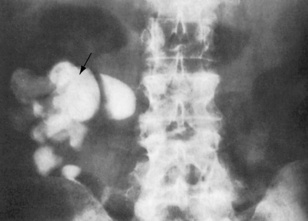

image

Fig. 8.16 This plain abdominal radiograph shows a large staghorn calculus (arrow) in the right kidney in a patient who presented with recurrent urinary tract infections.

(From Williams G, Mallick NP, 1994. Color atlas of renal diseases, 2nd edn. Mosby Year Book.)